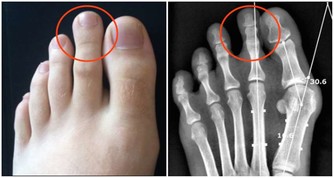

4.剪腳趾甲時,身體彎曲是否有不適感?

如果伸展時覺得很吃力,就要重視你的關節和骨質情況,當心關節炎,骨質疏鬆等疾病找上門,這也可能是心臟出問題的警訊,建議每天5分鐘的伸展練習能改善這種狀況。